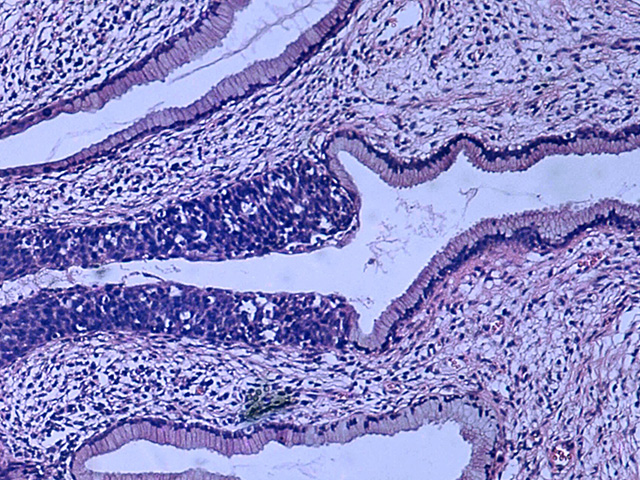

Женщин с положительным результатом направляли на кольпоскопию и биопсию, а наличие серьезных поражений подтверждали гистологически. Женщины с отрицательными результатами обоих тестов считались здоровыми. Ученые оценивали, насколько хорошо каждый метод выявляет цервикальную интраэпителиальную неоплазию второй и третьей степени и выше (CIN2+/CIN3+). Чувствительность анализа менструальной крови составила 94,7%, тогда как у образцов, взятых врачами, – 92,1%. Специфичность была немного ниже: 89,1% против 90,0%.